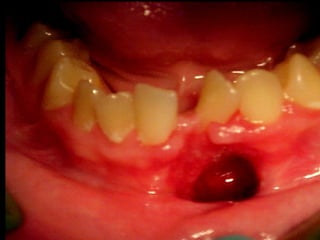

Eliminación de focos sépticos en bloque en paciente con osteitis

mandibular crónica

Nótese como en este caso la paciente tiene tomadas las regiones geniana,

palpebral, maseterina, temporal y región lateral del cuello.

En este acercamiento pueden observar con más claridad la gravedad del caso.

El manejo se hizo con triple

esquema: Cefotaxima, Clindamicina

y metronidazol, por supuesto estos

pacientes son rigurosamente

aislados.

En el estudio radiográfico determinamos que el factor causal fué un foco séptico

dentario a nivel de segundo molar inferior izquierdo.

Después de 14 días de hospitalización la paciente es egresada con un mejor

pronóstico. Habiendo drenado compartimientos aponeuróticos.

En esta imagen pueden apreciar

como la infección además de

fibrosis muscular ha determinado

lesión del nervio facial. Por lo que

se envía a fisioterapia.